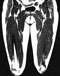

CT of adductor canal 7. Clean and identify the blood vessels of the anterior and medial thigh. (Play movie; View images: N 500, 501, 502, 504, 512, 544, TG 3-02, 3-22, 3-23, 3-27, 3-29, 3-62)

Coronal section of the thigh Coronal section of the thigh Coronal section of the thigh 9. Clean and identify the muscles and nerves of the medial femoral compartment. (Play movie; View images: N 490, 491, 492, 493, 497, 498, 500, 501, 539, TG 3-12, 3-13, 3-14, 3-19, 3-20, 3-21, 3-24, 3-57, 3-64)

Cross section of the thigh